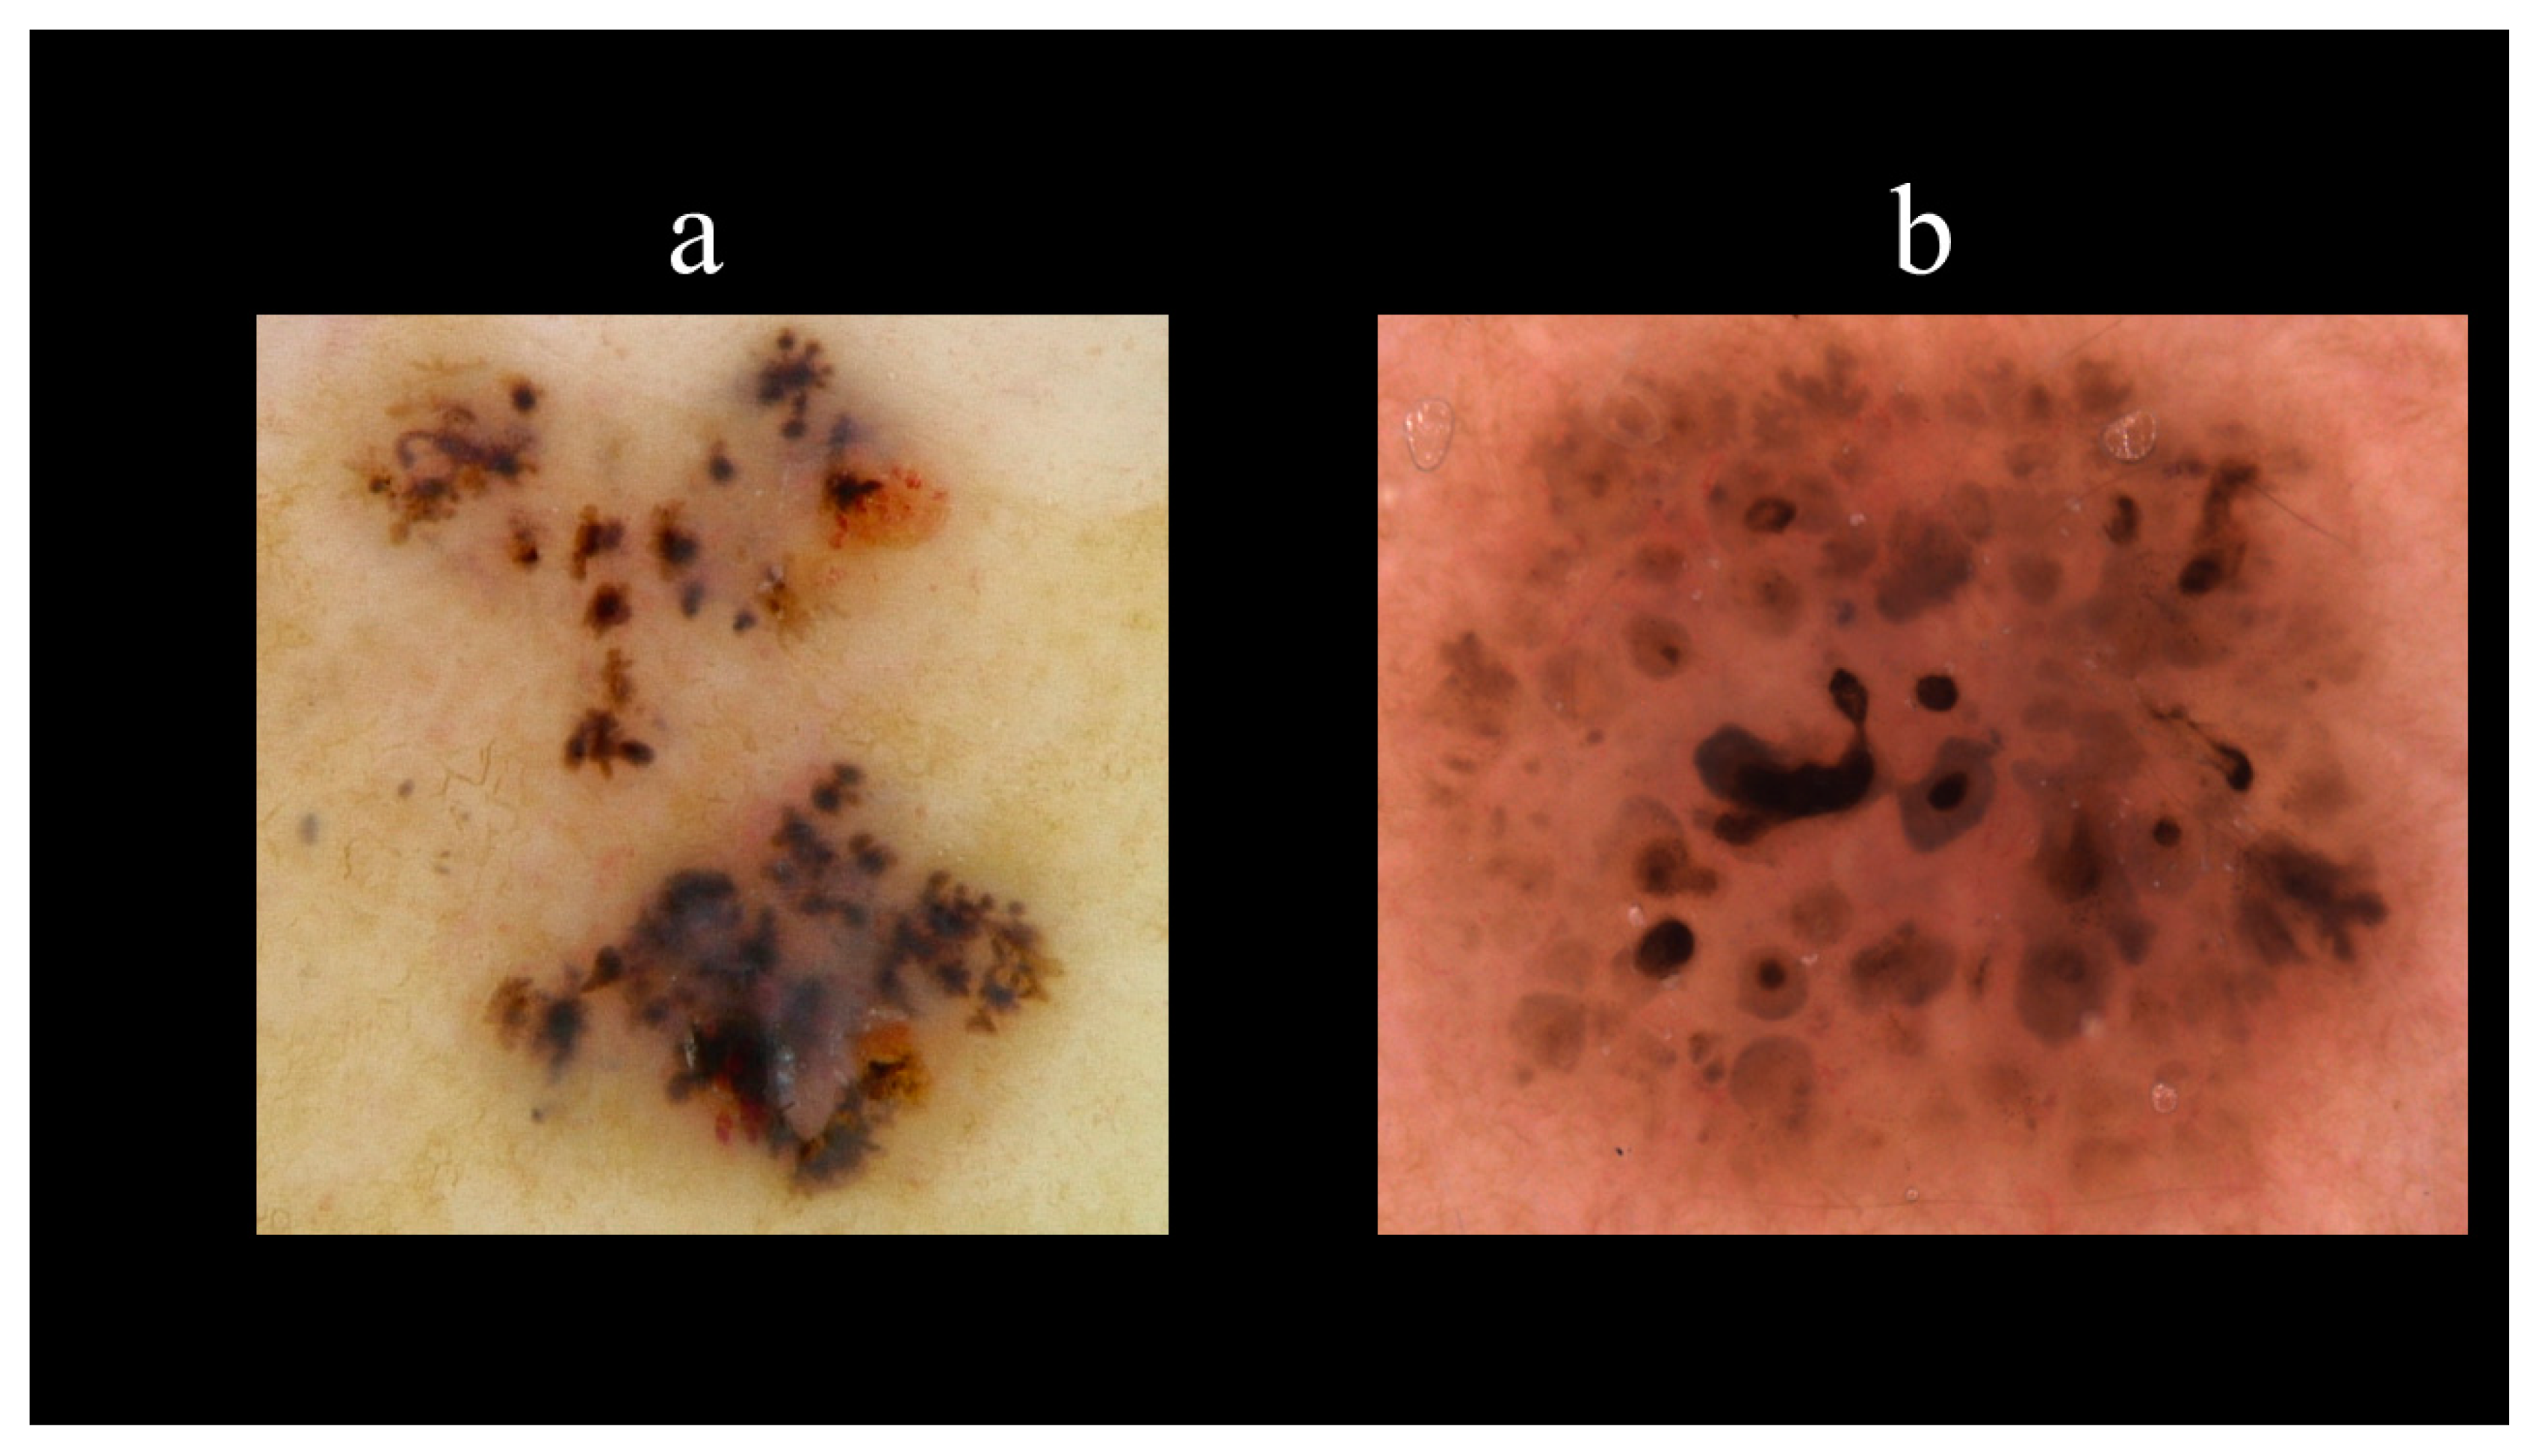

5. Dermoscopy